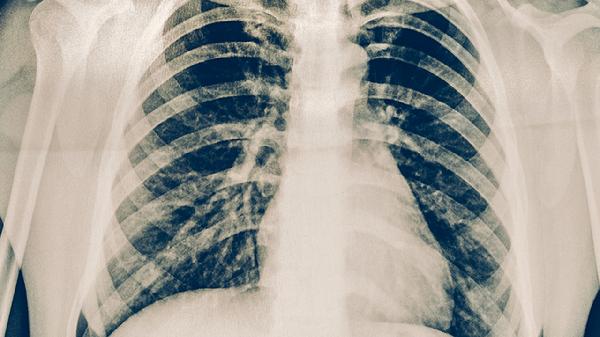

肺结核疾病的症状是什么

肺结核的症状主要有咳嗽、咳痰、咯血、胸痛、发热等。肺结核是由结核分枝杆菌感染引起的慢性传染病,多累及肺部,也可侵犯其他器官。

肺结核患者应注意保持室内空气流通,避免密切接触他人以防传染。饮食上应保证充足热量和优质蛋白摄入,多吃鸡蛋、牛奶、瘦肉等食物。适当进行散步等轻度运动,但避免过度劳累。严格遵医嘱规范用药,不可自行停药或减量,定期复查胸部影像学和痰结核菌检查。出现咯血、呼吸困难等症状加重时应立即就医。